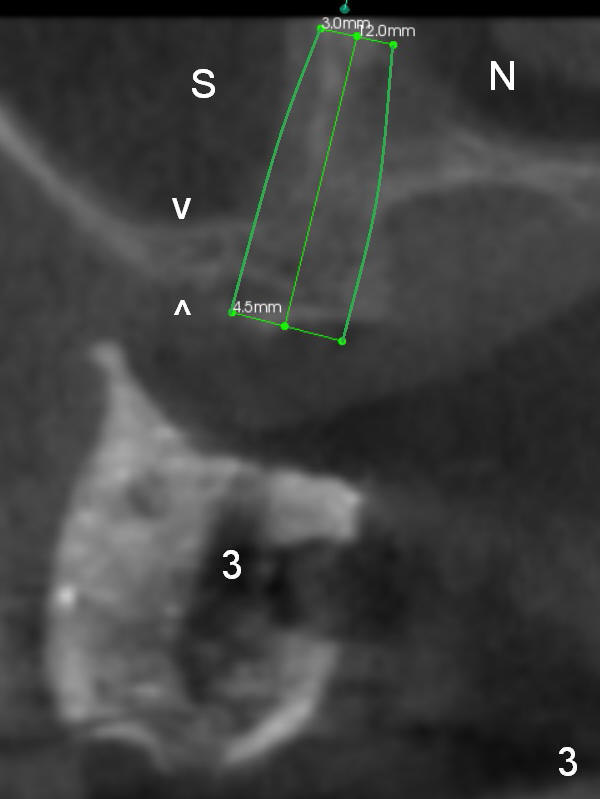

As mentioned earlier, the 56-year-old man is taking Plavix, one tablet every other day. The last time he took the medication is 4 days ago. For hemostasis, three carpules of 2% Xylocaine with 1:50,000 Epinephrine are administered in infiltration. Initial osteotomies are established through the CT scan stent (Fig.1-4: #2-4). Then an incision is made. After raising the flap, the osteotomy sites are checked. Ridge split is made between these sites with a chisel without much success. Bone is soft between #2 and 3. Sinus lift (Fig.2,4) is attempted at #2 and 4 (3.6 mm), whereas bone expansion is accomplished at #3, in the bone between the sinus (Fig.3 S) and the nasal cavity (N).

After use of 2.8 mm round bur at #4 for sinus lift, a 4x8.5 mm regular drill is used with resultant sinus membrane perforation at the sinus floor. The latter is repaired with insertion of Osteogen plug prior to place 4.5x8.5 mm implant (Fig.5,6). The similar mistake occurs at #3: after using 2.4/3.7 mm bone expander for 10 mm, a 4x10 mm is used, which also results in sinus perforation, probably sideway, buccally. Trimmed Osteogen plug is placed before a 4.5x10 mm implant is placed with primary stability (Fig.6). The reason for use of the regular drills is to avoid ridge fracture due to under prep.

In fact, these implants seem to heal normally 2.5 months post (Fig.10). After change in abutments at #2 (from 5.5x7(4) to 4.5x5.5(5) mm) and #4 (from 5.5x7(2) to 4.5x5.5(1) mm) and torquing, impression is taken. The implant at #3 appears to be associated with the septal bone (Fig.10 *). There is no apparent bone loss 1 years 4 months post cementation (Fig.11). The patient will return for 14,15 implants.